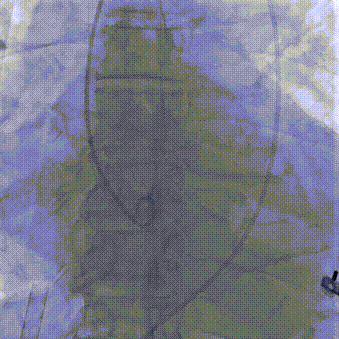

导丝成功跨瓣,经输送系统送入SAPIEN 3 29 mm瓣膜,顺利过弓并成功跨瓣;

输送系统顺利过弓

导丝成功跨瓣,经输送系统送入SAPIEN 3 29mm瓣膜,顺利经过迂曲的主动脉段,顺利过弓并成功跨瓣;

输送系统成功穿过迂曲主动脉段